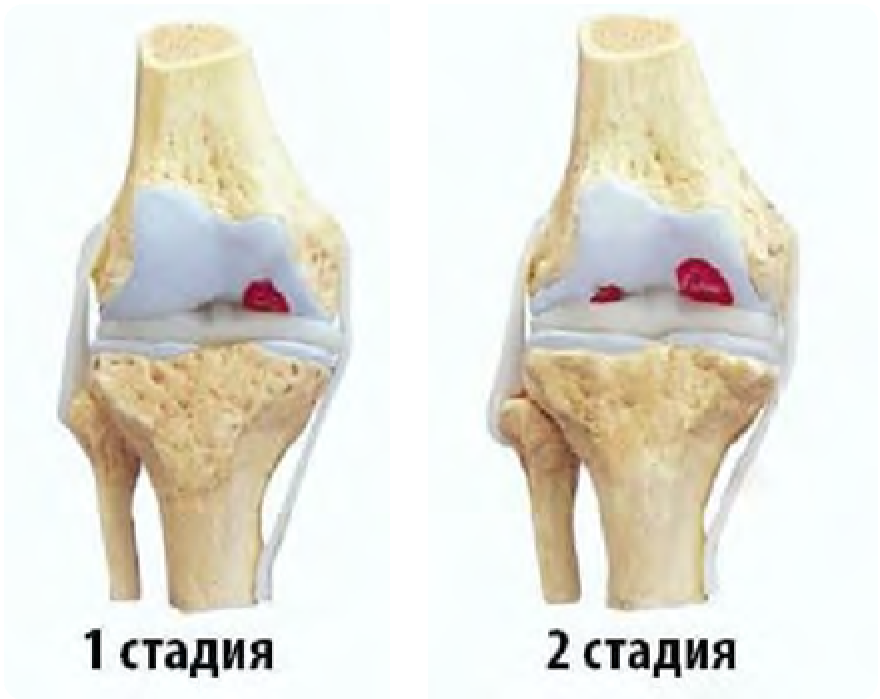

Боль и нарушение функции – основные симптомы

Рекомендовано ортезирование, короткими курсами при обострении и преимущественной локализации артроза в бедренно-надколенниковом сочленении(уровень В2)